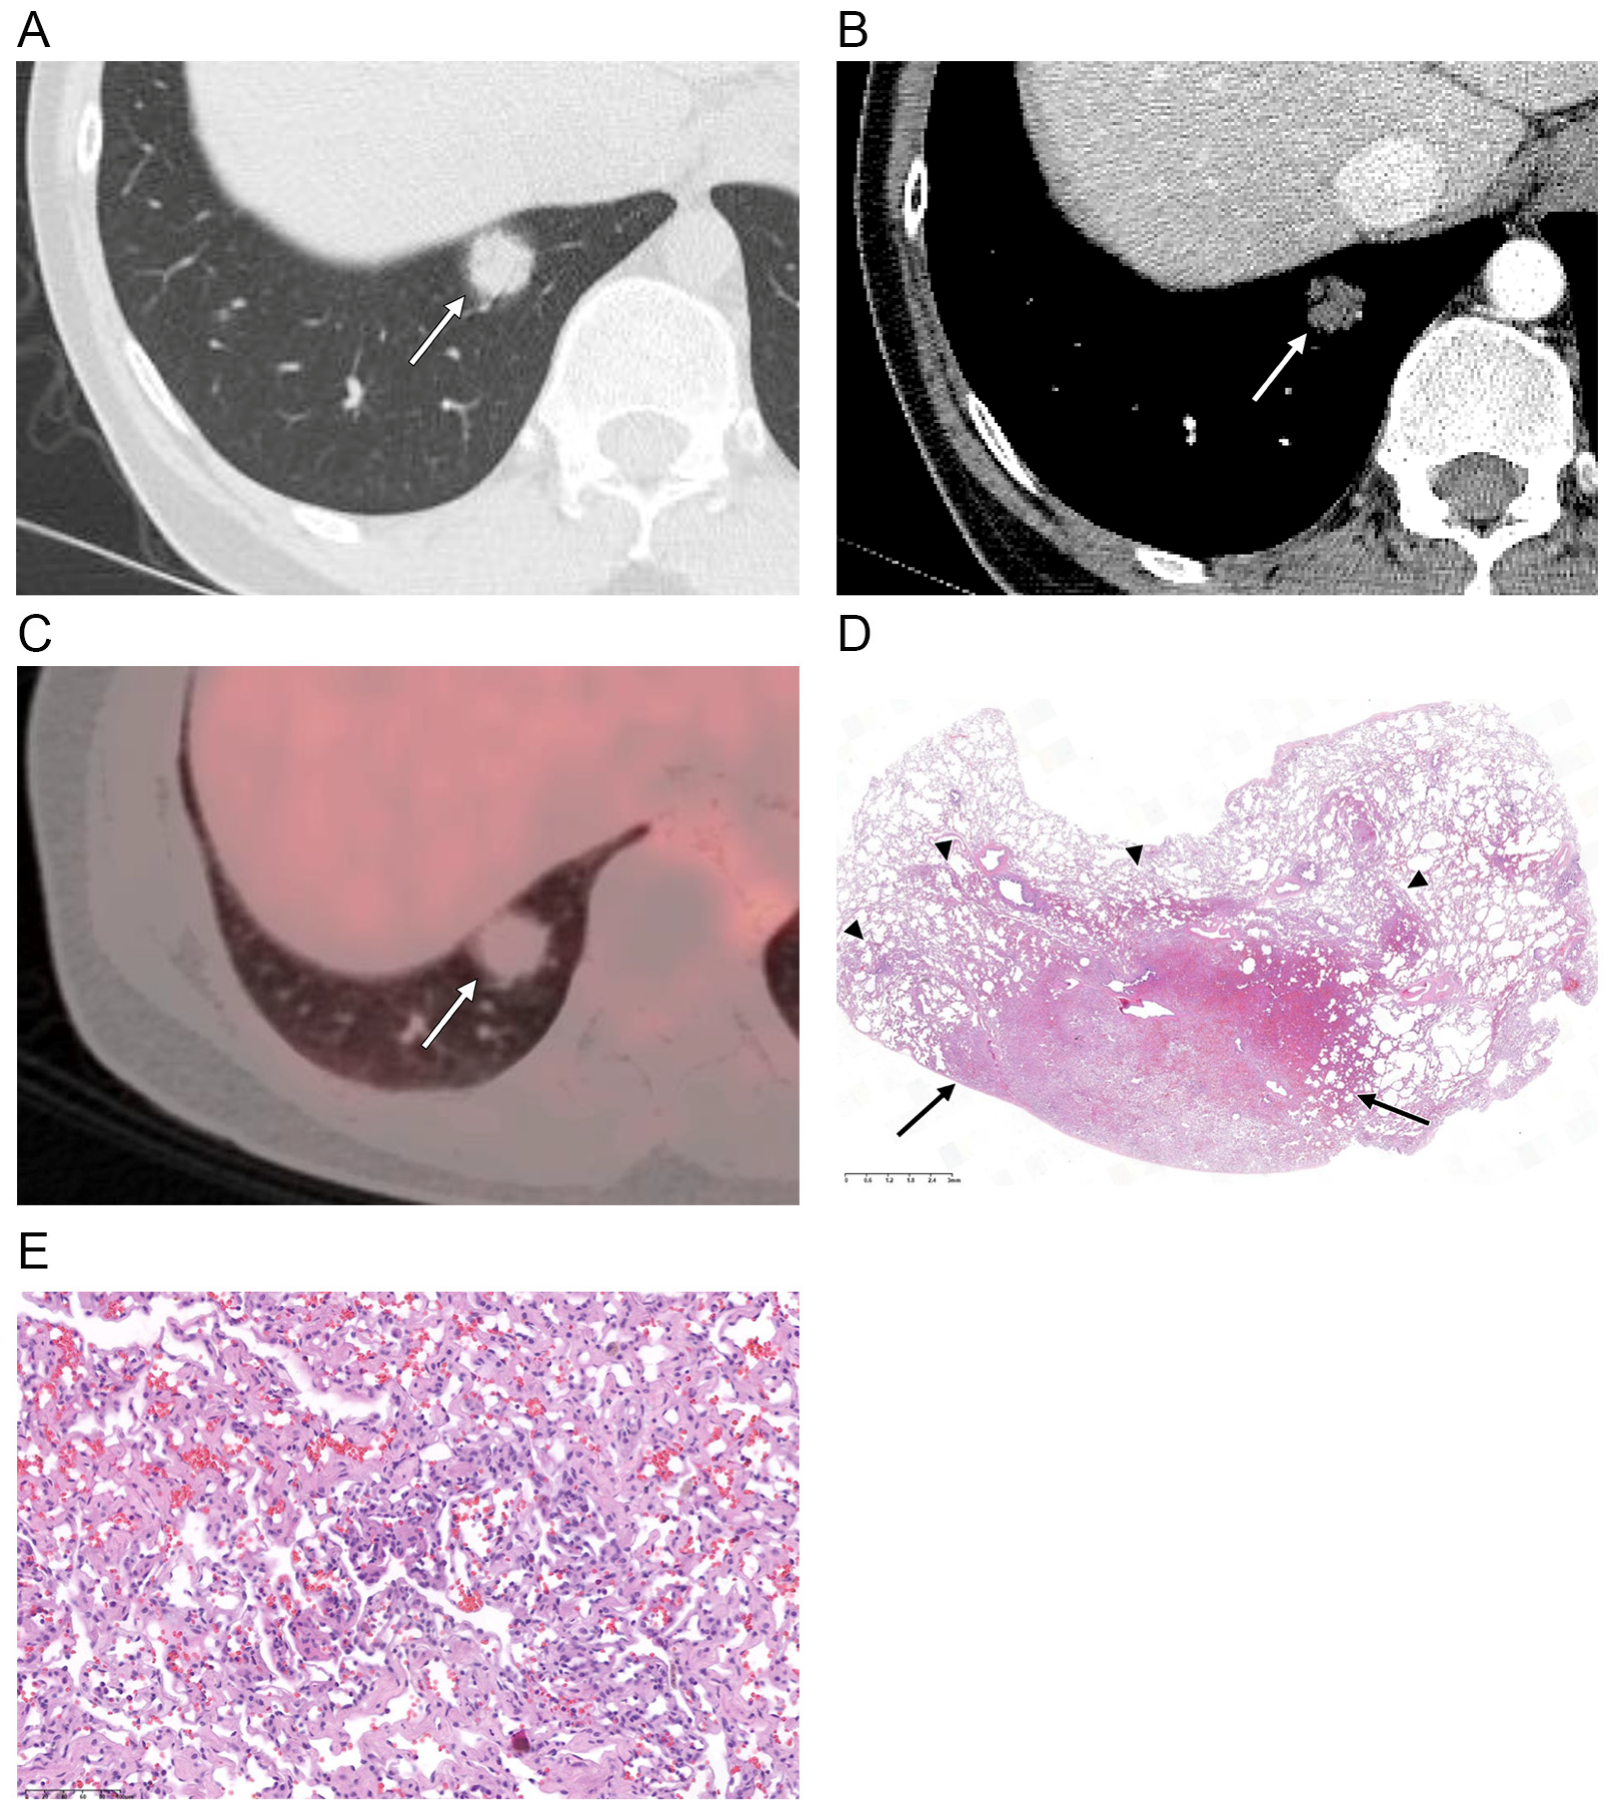

| Nodule density | |

| Ground-glass | 1 (6) |

| Part-solid | 15 (88) |

| Solid | 1 (6) |

| Perivascular lucency | 2 (12) |

| Air bronchogram | 10 (59) |

| Pleural retraction * | 0 (0) |

| Enhancement ** | |

| Hypoattenuation | 14 (93) |